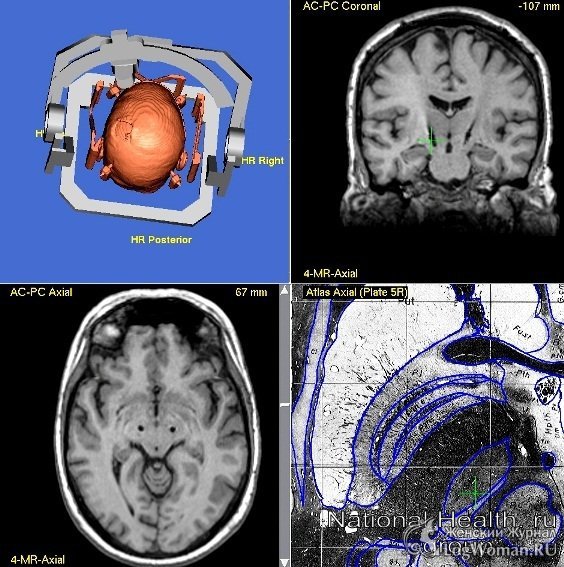

Хирургические методы лечения болезни Паркинсона

Болезнь Паркинсона чаще всего проявляется в пожилом возрасте. Причины её точного появления определить трудно, но специалисты сходятся во мнении, что предопределяющим фактором выступает генетическая...